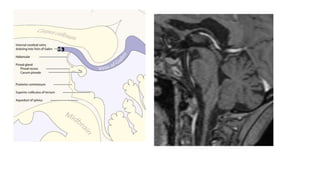

Pineal gland

• The pineal gland is an encapsulated , extra axial structure.

• 1 to 3 % of all intracranial neoplasms.

• Avg measurements : 7.4 mm in (L), 6.9 mm in (W), and 2.5 mm in (H)

• Pineal masses originate infratentorially and expand into the posterior third

ventricle.

• Malignant tumors, particularly of glial origin, can invade into the midbrain

and thalamus.